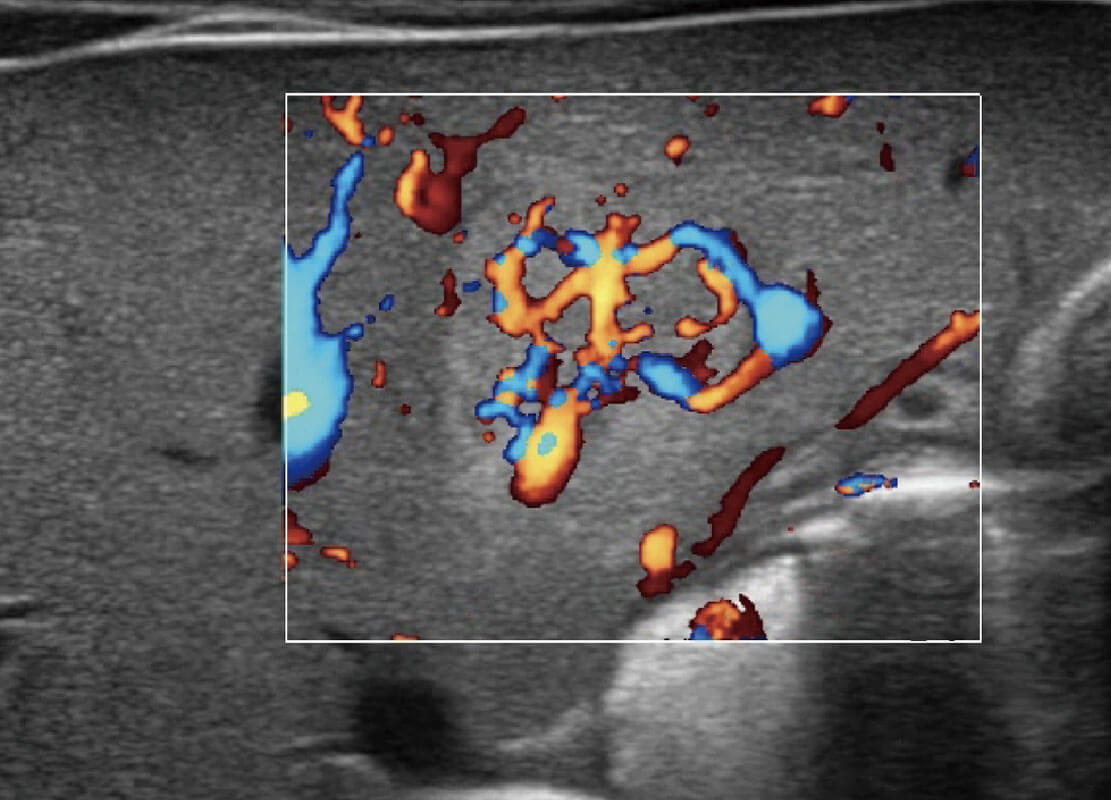

• 新生儿肝血管癌

• 新生儿脊髓圆锥

• 新生儿心脏

乳腺超声 / 新生儿

P60搭载宽频带线阵探头、宽景成像、弹性成像技术,为您提供乳腺应用方案。P60支持高频相控阵探头、线阵探头、腹部高频探头、腹部微凸探头等,丰富的探头群搭载敏感的彩色血流成像,适用于新生儿多种脏器检测要求,满足新生儿筛查需求。